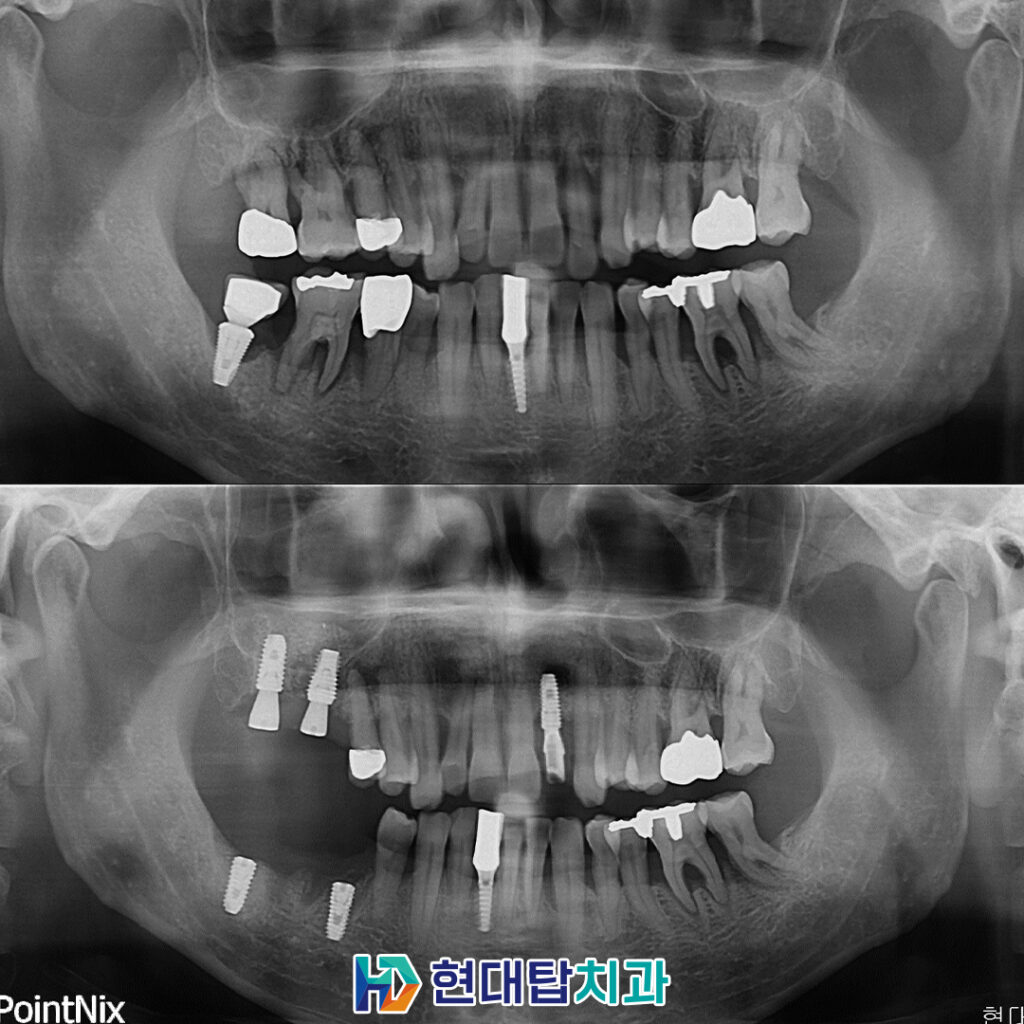

전반적으로 만성 치주염이 오랜 기간

지속되어 오신 상태로 잇몸뼈가

녹아있는 부분이 많이 관찰되었습니다.

또한, 오른쪽 위, 아래 모든 어금니 부위

예후가 불량한 상태였고, 왼쪽 앞니도

염증으로 인해 흔들림이 있는 상태였으므로

살려서 쓰기 힘든 치아들을

발치한 후 임플란트를

수면으로 진행하시기로 하였습니다.

기존 오른쪽 아래 임플란트 또한

임플란트 주위염으로 인해 제거가

불가피한 상황이었습니다.

울산동구임플란트 잘하는곳 TOP치과에서는

임플란트를 식립한 후 인공치근과

잇몸뼈가 융합될 수 있도록 충분한

기간을 기다려준 후 보철물의 제작을

진행하고 있습니다.

또한, 왼쪽의 앞니 경우에는

뼈이식을 동반하여 임플란트 식립과

당일 보철치료까지 모두 안정적으로

완료하였습니다.